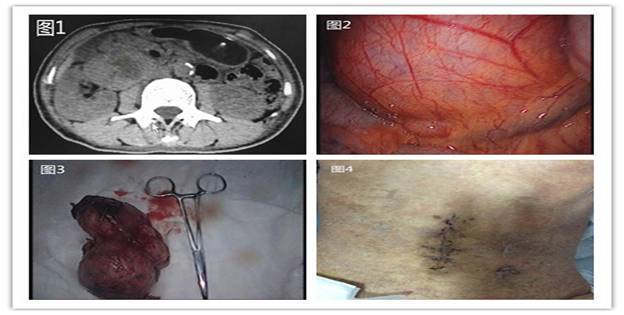

據(jù)悉,59歲的患者羅阿姨在7-8年前就已發(fā)現(xiàn)腹腔內(nèi)一腫塊,當(dāng)時僅“核桃”大小,因沒有任何不適,所以也就沒引起重視。直到近日,因“糖尿病、皮膚濕疹”入住我院內(nèi)分泌科,查體顯示,右下腹可捫及一約6cm*5cm大小包塊,邊界清,無明顯壓痛,全腹CT檢查發(fā)現(xiàn)其右側(cè)中腹部可見一約11cm*6cm*6cm巨大混雜密度包塊,周圍臟器受壓明顯(圖1)。為求外科治療,轉(zhuǎn)入胃腸外科。經(jīng)過仔細分析病例、閱片,發(fā)現(xiàn)該患者腹腔內(nèi)的巨大腫瘤位于腹膜后,已累及腹腔重要血管、神經(jīng)及臟器,手術(shù)難度較大。結(jié)合患者既往糖尿病多年,血糖控制差,若行傳統(tǒng)開腹手術(shù),術(shù)后切口感染、愈合又是一難題;若不進行手術(shù),巨大腫瘤將有繼續(xù)壓迫臟器、甚至破裂可能,以致威脅生命。為此,在譚曙光主任的帶領(lǐng)下,全科人員反復(fù)研究病例,考慮腹腔鏡手術(shù)具有創(chuàng)傷小、恢復(fù)快、鏡下視野清晰、安全可靠等優(yōu)點,決定行腹腔鏡微創(chuàng)手術(shù)。

術(shù)中探查發(fā)現(xiàn),腫塊位于右側(cè)結(jié)腸旁溝、右腎下極與十二指腸降部間隙(圖2)。由于腫塊較大,術(shù)中盡量游離周圍臟器、血管,進而形成“圍攻式”完整剝離腫塊,術(shù)中失血約20ml。經(jīng)過約2個小時的努力,埋在患者體內(nèi)的這枚“定時炸彈”被順利摘除(圖3)。術(shù)后患者腹部切口愈合良好(圖4)。